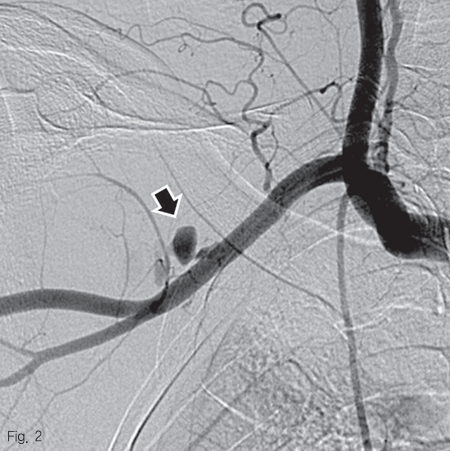

우측 대퇴동맥을 천자하여 5 Fr sheath를 거치 후, 0.035 인치 guidewire (Terumo Corp., Somerset, NJ, USA)를 이용하여 5 Fr Headhunter catheter (Cook Medical, Bloomington, IN, USA)를 팔머리동맥 근위부에 위치시킨 후 동맥 조영술을 시행하였다. 우쇄골하 동맥과 액와 동맥의 경계 부위의 위측에 조영제의 혈관외유출과 이로 인한 가성동맥류 형성을 확인하였다 (Fig. 2). 조영제 유출이 보이는 동맥의 직경은 약 6.2 mm 였으며, 거치된 카테터를 통해 Amplatz super stiff wire (Boston scientific, Natick, MA, USA)로 교체 후, 이 부위를 8 mm 직경의 4 cm 길이 자가팽창 covered 스텐트-그라프트 (vascular stent-graft, TaeWoong Medical, Gimpo, Korea)를 삽입하였다 (Fig 3A). 시술 후 우쇄골하 동맥조영술을 시행하였을 때 조영제 유출은 보이지 않았으며 (Fig. 3B), 우측 흉견봉동맥, 외측흉동맥, 견갑하동맥의 혈류가 잘 관찰되었다.

Fig 2

Digital subtraction angiography shows active extravasation of contrast media from right subclavian artery, with formation of a small pseudoaneurysm (arrow)